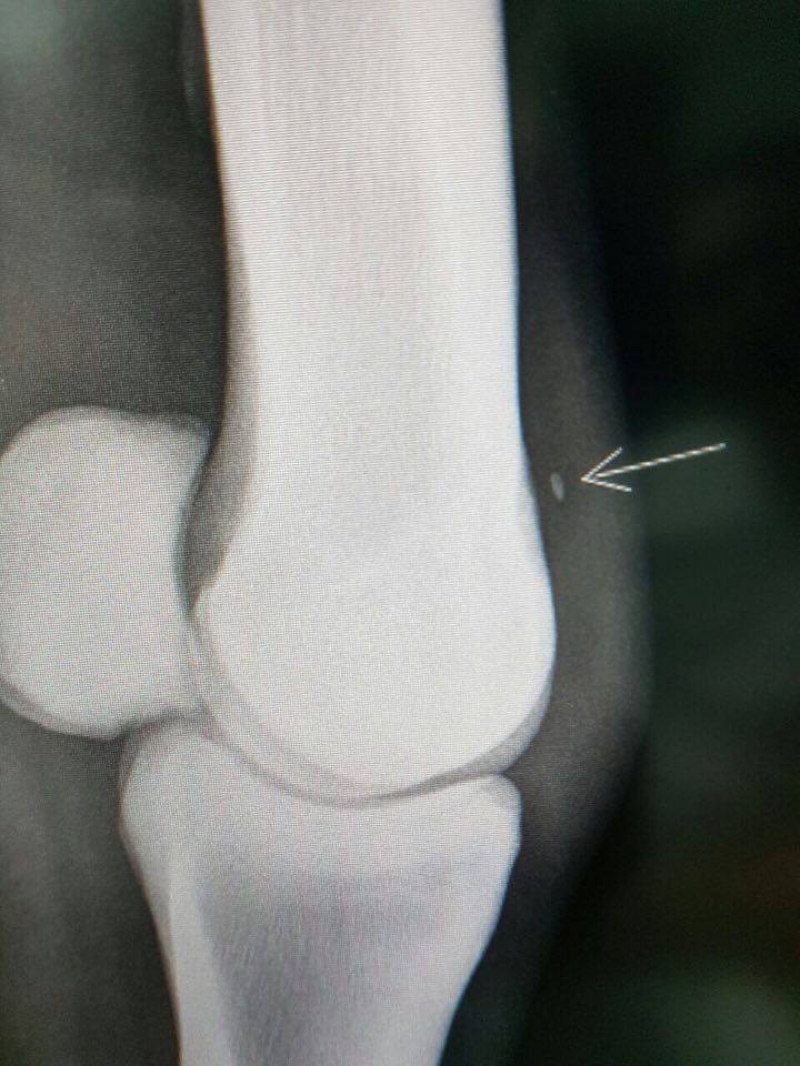

Há cerca de três semanas, a equipe do Hospital Veterinário da FAG diagnosticou uma osteocondrite dissecante em uma égua usada em provas de baliza e tambor, de Toledo. Em palavras simples, o problema era uma fratura de cartilagem, que deixou um fragmento solto na articulação. Após perceber que o membro anterior esquerdo do animal estava com algum problema, o dono o trouxe para o Hospital, onde uma radiografia descobriu o motivo da dificuldade, e uma cirurgia foi marcada.

A égua de alto valor foi internada na última segunda-feira (12), para permanecer em jejum e ser preparada para a operação. O procedimento cirúrgico aconteceu na terça-feira (13) e foi conduzido pelo cirurgião da Universidade Federal do Paraná, Peterson Triches, que veio de Curitiba para a operação, com apoio da equipe do Hospital Veterinário FAG. A égua passou por uma Artroscopia para a remoção do fragmento. "É uma cirurgia pouco invasiva, com anestesia geral. São feitas duas incisões, bem pequenas, de menos de 1 cm: em uma é colocada uma lente com luz e uma câmera, e por outro orifício entra o material cirúrgico utilizado. Acompanhamos tudo por um monitor. A cirurgia demorou cerca de 50 minutos. Mas foram três horas no total, entre a sedação e a remoção do animal até a baia", contou o Diretor do Hospital, Rennê Gomiero.